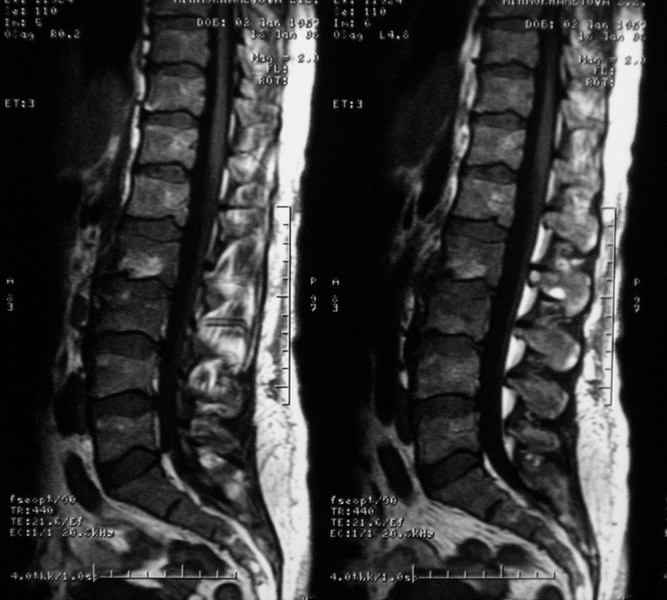

Отправляю MRI в динамике, снятые с пленки на фотоаппарат.

Имя     : при_госпитализации.jpg